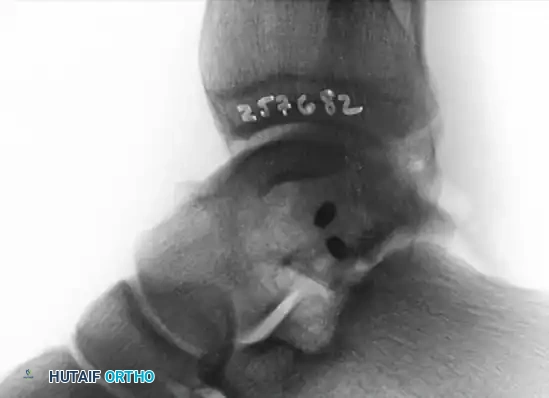

Postoperative Anteroposterior (AP) radiograph showing anatomic reduction and stabilization of the lateral process.

Postoperative lateral radiograph confirming the placement of fully countersunk screws, ensuring no intra-articular hardware prominence.